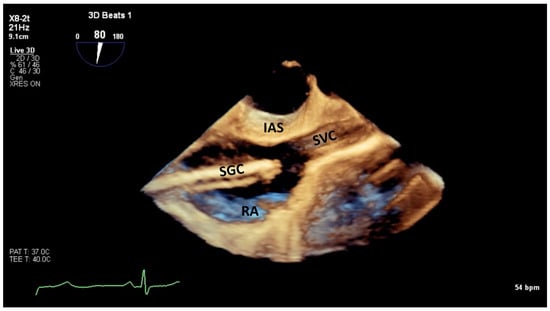

6.1. TEE-Guided Tricuspid TEER